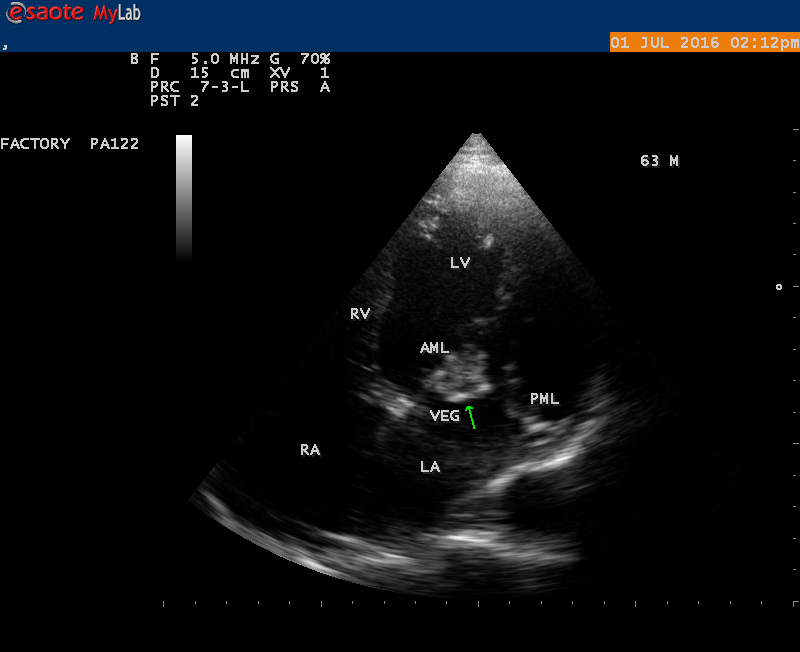

The most common and direct evidence of infective endocarditis is the vegetation and it begins as a microscopic focus of infection and gradually grows into a conspicuous mass. It is typically an irregularly shaped, highly mobile, echogenic mass attached to the free edge of a valve leaflet ( most commonly at the coaptation line) and tends to develop on the ‘upstream’ side of the valve leaflets ( ie, the ventricular side of aortic valve and the atrial side of mitral and tricuspid valves. They may be seesile or pedunculated, but usually has an oscillating or fluttering motion, a typical feature of most vegetations. Vegetation move with the leaflet in a more chaotic (‘oscillating’) manner and it may prolapse through the valve into the LV (left ventricle) as it opens as shown in Figures 3, 4 and 16 and into LA (left atrium) as it closing (Figure 5 and 6) . The mass of vegetation is typically homogeneous with echogenicity similar to that of the myocardium. The infectious process often alter the valvular structure and function. Extensive involvement of the leaflet may result in chordal rupture, leading to severe regurgitation as shown in Figure 21 . Direct and typical signs of RMCT (ruptured mitral chordate tendineae) were chain-flail or whiplash-like changes and had an incidence of 86.7%, causing severe regurgitation and mitral chordal rupture is the leading cause of flail mitral leaflet[30]. A large vegetation may obstruct the valve orifice as shown in Figure 1 and 2 , sometimes termed as “obstructive-type bacterial endocarditis” and producing a functional valve stenosis ( Ping-Pong mitral stenosis [31]) similar to left atrial myxoma as shown in Figure 29.

The shape and size of vegetation are quite variable and mostly it is polypoid [32]. The typical vegetation is a ‘sessile’ or ‘ pedunculating’ valve – attached mass. A ‘sessile’ vegetation had to be completely attached to the valve as shown in Figures 34 and 35 in a 63- year old male, in which a large vegetation is attached to the atrial side of anterior mitral leaflet [33-Figure 13.3-A], producing severe mitral regurgitation as shown in Figure 36 and a mobile vegetation showed a pedunculating part prolapsing into the ventricle as shown in Figure 3 and 4 or atrium as shown in Figure 5 [33-Figure 13.1] in a 10-year old female child. A vegetation was considered as ‘definite’ when shaggy echoes in the M-mode study as shown in Figure 20 . and a corresponding mass without restricted valve motion in the two-dimensional echocardiogram were found as shown in Figure 16 and 30 [33-Figure 13.7]. The vegetation vary in size, often being just a few mm and sometimes reaching to 2-3 cm. A vegetation must be atleast 3 to 6 mm in size to be reliably seen. The mean size of vegetation was 0.6 mm (range 3 to 28) and vegetation > 10 mm in diameter was defined as ‘large’ and those ≤ 10 mm in diameter was defined as ‘small’ and ≥ 15 mm is ‘very large’. Vegetations resulting from fungal infections (candida, aspergillus) are usually much bigger than bacterial vegetations and can be so big to be mistaken for a cardiac tumor. The large vegetations are at increased risk for embolic complications [34], especially on the anterior leaflet of the mitral valve with mobility [35]. A vegetation size of 3.2 x 4.4 cm is called as ‘giant vegetation’ on the mitral valve with a fibrillary appearance of the mass [36- Figure 3] as shown in Figure 1 is an important predictor of embolic phenomena in patients with infective endocarditis causing severe mitral regurgitation as ‘Duck’ shaped jets (Figures 24 and 25 ), disorganized (Figure 21) and sometimes the regurigitant jet splits into two components as one into LA and the second one into LV simultaneously as a bileaflet jets (Figure 10 ) similar to bileaflet structure of AML with vegetation masses (Figure 9 ) . The size of the largest vegetation reported on the mitral valve in the literature in patients with bacterial endocarditis is 7x4 cm[37]. In a study of Nunes, et al[38], vegetation size >13 mm was the only independent predictor of mortality, but some studies [39],[40] did not had an increased embolic risk in patients with vegetation focused only on its presence and size and not on their location. Embolic complications may occur in infective endocarditis(20.6%)and were not more prevalent in the groups with large vegetations [41]. However, Wong, et al [42] found an increased need for surgery in patients with a large vegetation (>10 mm).

The size and shape of vegetation vary due to curling of vegetation. The size of vegetation in this child is 35.6 x 9.3 mm as in Figure 17 , 20 x 23.7 mm as in Figure 1 , 32.9 x 13.9 mm as in Figure 2 .

The shape of vegetation varies in this child as ‘popcorn’ like (Figures 1,3 and 4 ), rod-shaped (Figure ), basket shaped (Figure 7 )[33-Figure 13.3], ‘baby in hand’ appearance (Figure 18), ‘cucumber shaped (Figure 2 ) and a ‘bunch of plantain’appearance (Figure 33 ), ring shaped (Figure 19 }, bileaflet structure (Figure 9 )with bileaflet MR jet as shown in Figure 10 . and kissing forms (Figure 13 - parasternal long axis view, Figure 14 - apical four chamber view and Figure 15 - short axis view)